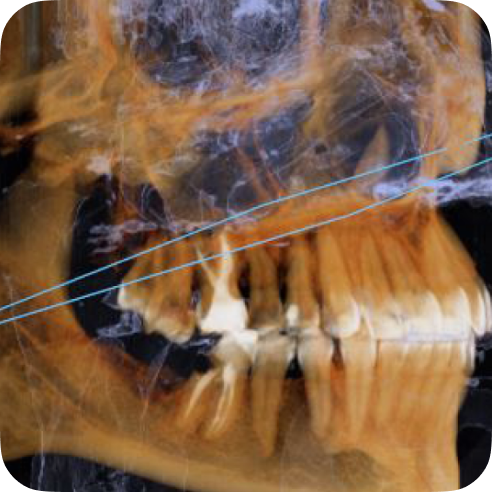

Компания DEXIS, известная ранее как KaVo, помогает трансформировать клиническую практику и преображать улыбки пациентов. Более 150 000 аппаратов DEXIS уже применяют стоматологи во всем мире. В портфеле рентгенологического оборудования DEXIS представлены интраоральные рентгеновские аппараты, аппараты для выполнения качественных панорамных и цефалометрических снимков, компьютерные томографы для стоматологии и высокопроизводительное программное обеспечение для 3D-диагностики.

Компания DEXIS, известная ранее как KaVo, помогает трансформировать клиническую практику и преображать улыбки пациентов. Более 150 000 аппаратов DEXIS уже применяют стоматологи во всем мире. В портфеле рентгенологического оборудования DEXIS представлены интраоральные рентгеновские аппараты, аппараты для выполнения качественных панорамных и цефалометрических снимков, компьютерные томографы для стоматологии и высокопроизводительное программное обеспечение для 3D-диагностики.

Компания DEXIS, известная ранее как KaVo, помогает трансформировать клиническую практику и преображать улыбки пациентов. Более 150 000 аппаратов DEXIS уже применяют стоматологи во всем мире. В портфеле рентгенологического оборудования DEXIS представлены интраоральные рентгеновские аппараты, аппараты для выполнения качественных панорамных и цефалометрических снимков, компьютерные томографы для стоматологии и высокопроизводительное программное обеспечение для 3D-диагностики.